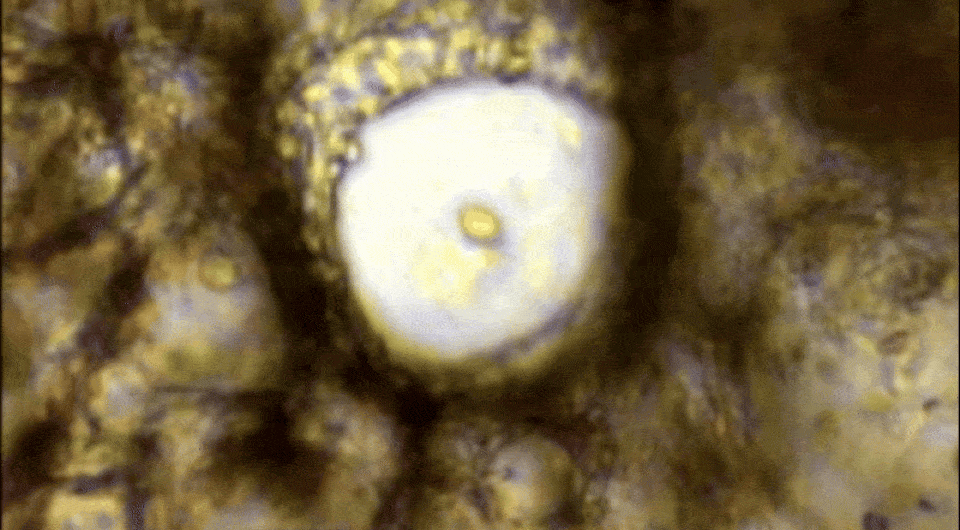

Dustin C. Bagley et al. / Science, 2024

Перейдя в Лондонский королевский колледж, Розенблатт с коллегами из Великобритании, Испании и США занялась изучением возможной роли этого механизма в патогенезе астмы. Для этого они воздействовали метахолином на ex vivo срезы мышиных бронхов, подвергавшихся или не подвергавшихся первичному контакту с аллергенами. В течение 15 минут после такого воздействия в малых и средних бронхиолах наблюдалась выраженная экструзия эпителия — высота клеточного слоя увеличивалась в среднем на 196 процентов, причем это положительно коррелировало с дозой препарата и степенью бронхоконстрикции. Дальнейшие эксперименты показали, что β2-агонист альбутерол расслабляет бронхи после 15-минутной констрикции, но не предотвращает экструзию и разрушение эпителиальных клеток. Более того, при резком расширении бронхов под действием препарата эпителий зачастую отрывался от гладкомышечного слоя, что усугубляло повреждение.